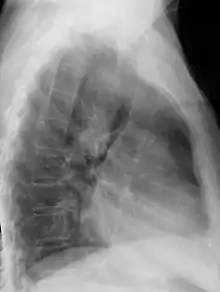

Anterior-posterior chest radiograph showing a right-sided aortic arch |

After birth, a right-sided aortic arch is visualized on chest radiography, by the aortic knob (the prominent shadow of the aortic arch) that is located right from the sternum instead of left. Complex lesions are often assessed by MRI or CT.